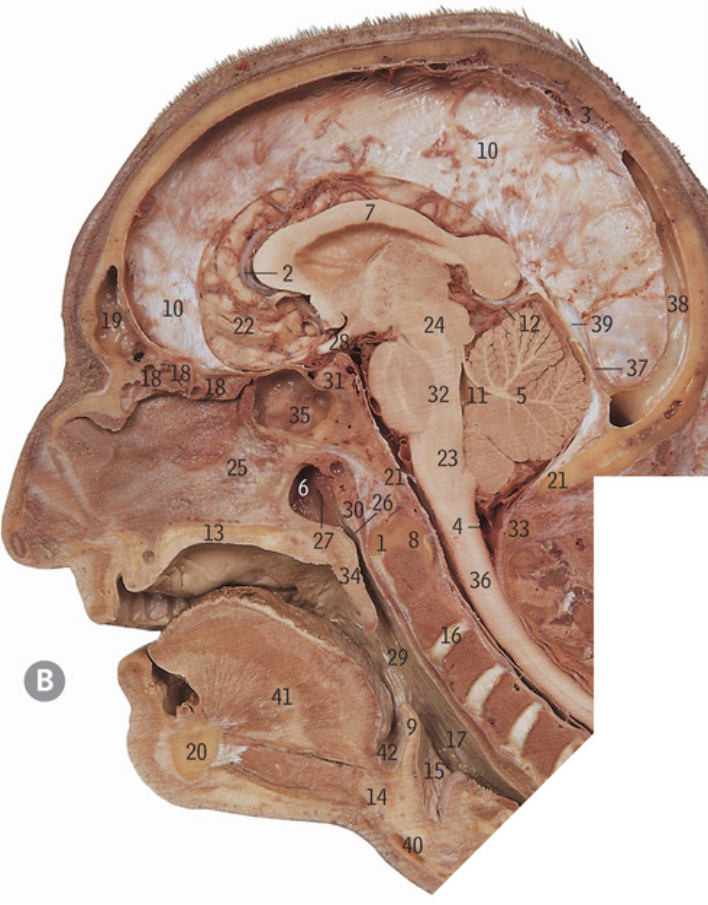

5

Cribiform plate

6

Crista galli

17

Greater wing of sphenoid bone

32

Lesser wing of sphenoid bone

38

Pituitary fossa

34

Optic canal

42

Superior orbital fissure

12

Foramen ovale

13

Foramen rotundum

14

Foramen spinosum

27

Hypoglossal canal

11

Foramen magnum

Superior nasal concha

Middle nasal concha

Ethmoidal air sinuses

Frontal air sinus

Lateral pterygoid plate

Medial pterygoid plate

Supra-orbital notch

Occipital condyle

Superior nuchal line

What cranial nerves travel through the superior orbital fissure

CN III/3, IV/4, V1/ophthalmic, VI/6

What travels through the hypoglossal canal

Hypoglossal nerve

What travels through the formen magnum

Spinal cord, accessory nerve

What muscles attach to the superior nuchal line

Occipitalis and trapezius

37

Zygomatic process of temporal bone

18

Mastoid processÂ

Petrous part of temporal bone

28

Internal auditory meatus

9

Mandibular fossa

3

Carotid canal

46

Styloid process

47

Stylomastoid foramen

Inner ear

16

Middle ear

8

Crus cerebri

What does the circled area refer to

Interpeduncular fossa

26

Oculomotor nerve

What are the nerve fibres descending through the crus cerebriÂ

Corticobulbar fibres, corticospinal fibres